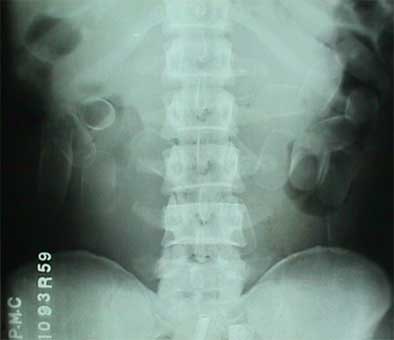

X-ray detected capsules in 59/70 patients (85%) and in all 70 patients (100%) imaged with CT. In these modalities the foreign bodies were seen as oval or rectangular densities surrounded by halos, said to represent air trapped within the Scotch tape or between two layers of condom. And for reasons the researchers do not yet understand, on CT the rims of the capsules were distinctively denser at 40 to 90 HU, while the centers were lucent at - 20 to -50 HU, Hussain said.

| Drug-bearing capsules with lucent halos can be seen in plain film image (above). In abdominal CT scout image (below), the lucent centers of the capsules contrast with denser rims. |